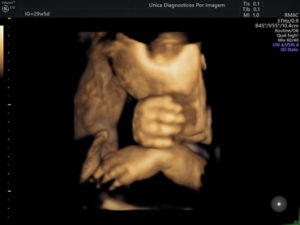

Exame importante que tem como objetivo avaliar a anatomia do feto e detectar possíveis malformações. Deve ser realizado preferencialmente realizado